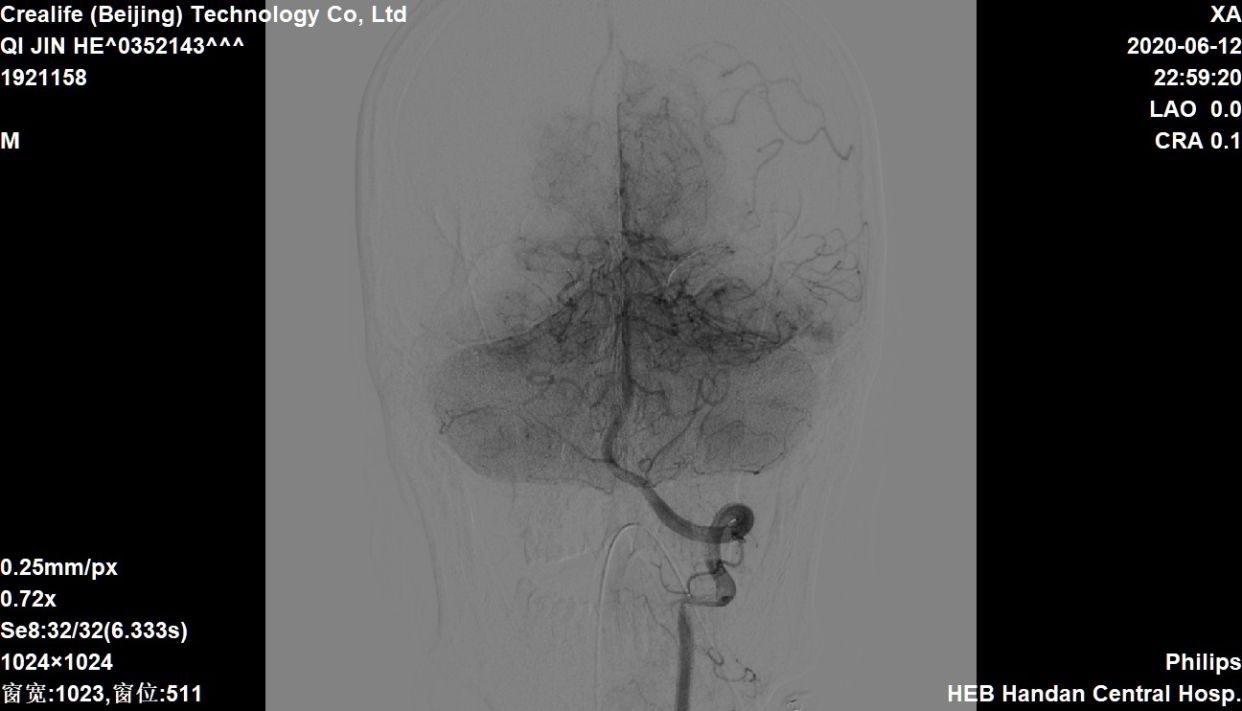

急性左侧大脑中动脉闭塞,考虑栓塞

释放支架后造影,提示有下干充盈缺损

支架配合抽吸导管取栓